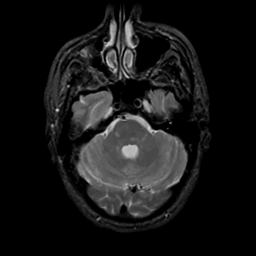

MR Study #20 October 6, 1991 -- Slice #13

[Home][Help][Clinical][Tour 1][Tour 2] Slice 13